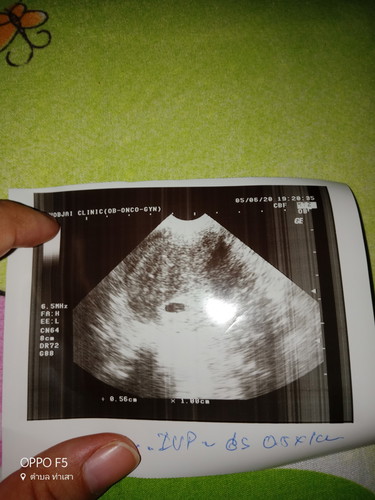

ท้องได้5สัปดาห์มีเลือดไหลนิดหน่อย

คือเราท้องได้5สัปดาห์แล้วค่ะตอนไปซาวหมอบอกว่าถุงตั้งครรภ์ไม่กลมมีโอกาสแท้งแต่แค่10%พอกลับบ้านมาได้ประมาน2วันมีเหลือดออกนิดนึงค่ะเมื่อวานมีแบบเป็นสีเข้มเหมือนเลือดประจำเดือนเก่ามีประมานปลายนิ้ว2นิ้วแล้วก้อหายไปพอมาวันนี้ทั้งวันไม่มีเลือดไหลนะค่ะจนตอนเย็นเราอาบน้ำแล้วเช็ดตัวถึงเห็นเลือดค่ะแต่คราวนี้เป็นสีแดงสดมีประมานปลายนิ้วเหมือนกันกังวลมากเลยค่ะกลัวจะแท้ง